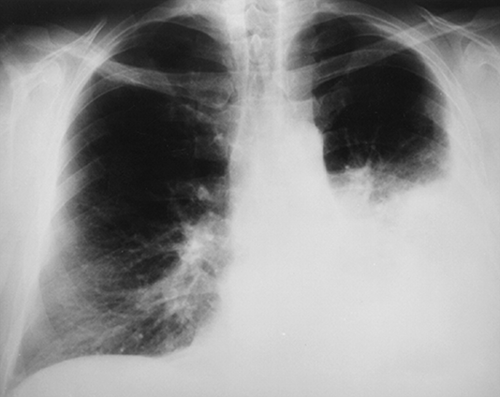

“My lupus is attacking my lungs. When I met Dr Bruwer, he didn’t give medication; all he did was do extensive tests, and he noticed something in my lungs, unlike other practitioners who gave me medicine that didn’t help,” she noted.